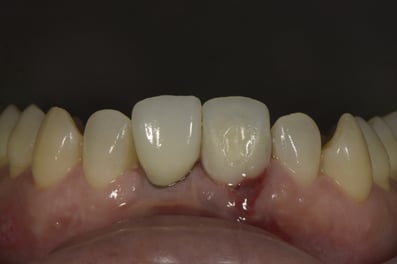

抜歯した直後にインプラントを埋入し、仮の歯を作製、唇側の骨のボリュームを保つために人工骨と結合組織を同時に移植する非常に優れた方法です。

Simplified Microscopic Implant surgical Lifelike Esthetics を略した手術名で、米国カルフォルニア州サンタバーバラで歯周病専門医として開業されていた、 Dr. Dennis Shanelec(故人)が考案した治療法です。抜歯した直後に仮歯を入れることによって,歯を取り巻く骨(硬組織)や歯肉(軟組織)の状態を維持できる非常に優れた方法です。しかし、手術としての難易度は非常に高いレベルに位置づけられます。